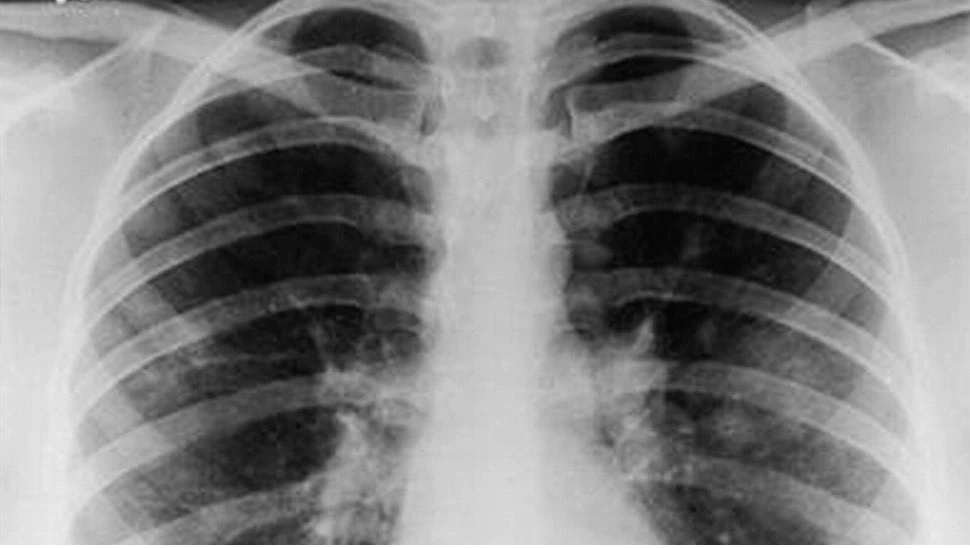

हम प्रतिदिन 350 लीटर ऑक्सीजन का उपयोग करते हैं। हमें अगर 3 मिनट तक ऑक्सीजन न मिले तो हमारी मृत्यु हो सकती है। कोरोना संक्रमण की इस दूसरी लहर में सबसे ज्यादा समस्या ऑक्सीजन की ही हो रही है। कोरोना के गंभीर संक्रमण में फेफड़े के अंदर निमोनिया हो जाता है तथा एयूट रेस्पिरेट्री डिस्टेंस सिंड्रोम भी हो जाता है। इन दोनों परिस्थितियों में रोगी की ऑक्सीजन काफी कम हो जाती है और रोगी की सांस फूलने लगती है।